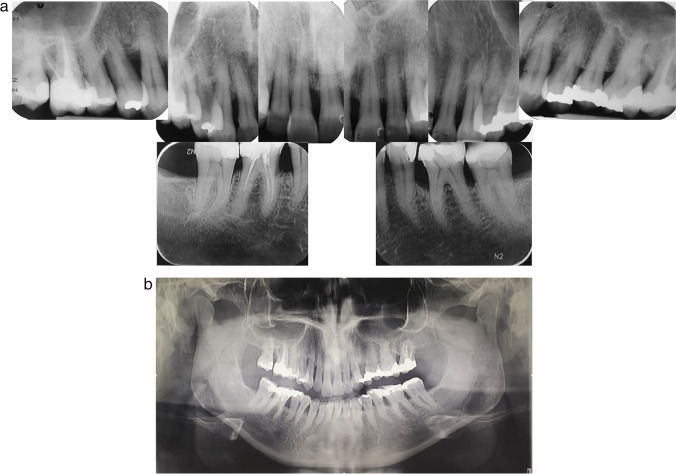

Since it is known that periodontitis can affect distinct jaw regions differently, a split-mouth design may limit the investigation’s scope. It seems sensible to test the MINST protocol using two parallel subject groups in the future. Due to the possibility of poorer response to the MINST protocol in smokers, it would be sensible to evaluate the effects of MINST on the treatment of suprabony periodontal defects in non-smokers and smokers separately, in addition, to evaluate a more recent version of MINST employing an anaesthetic without adrenaline and the use of curettes. To increase external validity, it would be necessary to study the efficacy of MINST in a broader range of patient populations, including patients with various healing disorders and non-academic clinical settings. Furthermore, the patient follow-up period may be extended to 1 year, and treatment outcomes may also be examined radiographically (Fig. 4).

Fig. 4.

a Local radiographs of a representative patient. b Orthopantomogram of a representative individual